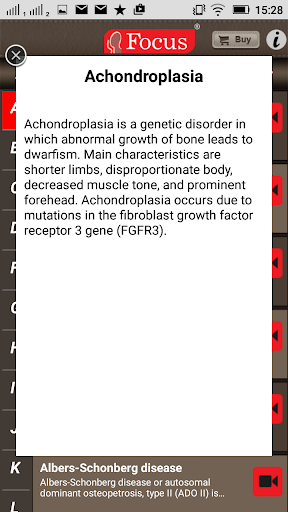

The FOCUS Animated Pocket Dictionary of RHEUMATOLOGY is the first ever animated dictionary in the subject. A valuable reference for physicians and students alike, it covers 100 rheumatology related terms and definitions. All the definitions have been graphically described with the help of 3D animations and are accompanied by text definitions.

The Focus Animated Pocket Dictionaries are the world’s first ever animated dictionaries that provide definitions of medical terms with the aid of realistic and narrated 3D animations, complimented with text definitions. Terms arranged alphabetically making definitions easy to search. These unique visual dictionaries are excellent reference sources for health professionals, students and health consumers. The videos play independent of the internet once downloaded.